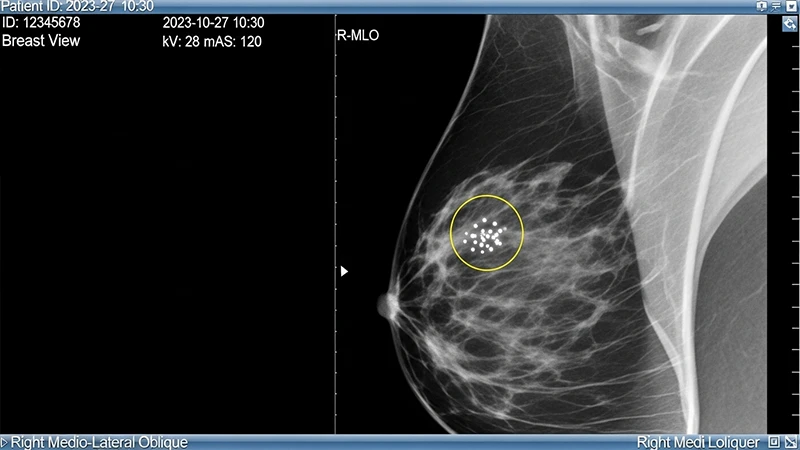

This is one of the earliest and most common applications of AI in imaging. A Computer-Aided Detection (or CADe) algorithm analyzes an image and places markers or circles on areas that it identifies as potentially abnormal. It acts as a "spell-checker" for the radiologist.

• In Mammography: CADe systems are trained to detect suspicious masses and clusters of microcalcifications, which can be an early sign of breast cancer.

The radiologist then reviews these marks. They use their expertise to decide if the AI's finding is a true abnormality or a "false positive" (e.g., normal overlapping blood vessels). The final diagnosis is always made by the human.

A mammogram image with an AI overlay showing a circle around a suspicious cluster of microcalcifications.